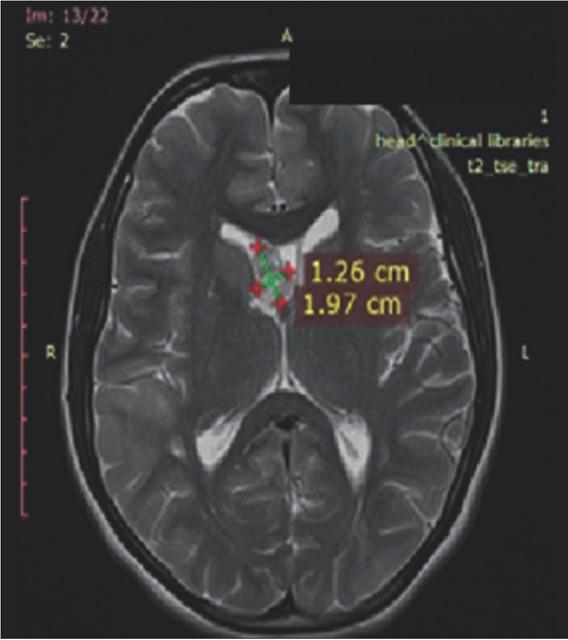

Figure 6

Magnetic resonance imaging of the brain at 36 months after everolimus treatment initiation.

Magnetic resonance imaging of the urinary tract and brain were performed before initiation of everolimus treatment (Figures 1 and 2). After 12 months of treatment, reduction of the renal tumors and SEGA were registered (Figures 3 and 4). At 36 months, ~24.0% reduction in the longest diameter of the largest AML in right kidney was achieved. Reduction of SEGA was also observed (Figures 5 and 6). All biochemical parameters remained stable during the follow-up period. Normal renal function without a new onset of proteinuria was observed (Table 2).

On the brain MRI, multiple lesions as subependimal nodules, subcortical tubers and largest tumor mass presented in foramen Monro as SEGA (diameter 3.0 × 1.5 cm) were described.

Due to the presence of a large brain structural manifestation, continuous follow-up by a neurologist and a neurosurgeon was performed. The majority of TSC patients have neurological symptoms, ~90.0% of affected individuals experience seizures and almost half also experience cognitive impairments, autism, or other behavioral disorders. Epilepsy is seen in 70.0-90.0% of patients, most commonly presenting in the first year of life [12]. Our patient had normal mental status without autism and/or behavioral difficulties. However, seizures were present from the first year of life, with prescribed therapy till 5 years. At the age of 12 years, when the new onset of seizures was registered, an anticonvulsive treatment was reinitiated. After many years free of seizures, the anticonvulsive therapy was again ceased. Thus, after 3 years undergoing everolimus therapy, a new episode of seizure was reported and anticonvulsive therapy was administered. The patient was placed on lamotrigin. The MRI findings excluded hydrocephalus without necessity of surgical treatment. Based on the literature, surgical intervention of SEGA >3 cm has 67.0% risk of surgery-related complications and surgery on tumors >4 cm was associated with 73.0% risk of complications [21,22].

It is recommended that SEGAs are MRI-monitored every 1-3 years in patients younger than 25, as these tumors usually grow in children and young adolescents, but do not have a tendency to grow in adulthood [21,22]. Similar case reports are found in the literature with similar disease presentation and medical treatment [23].